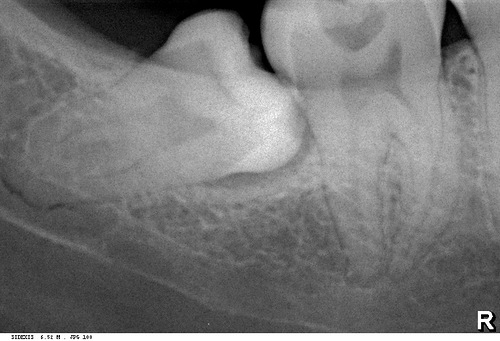

«на ортопантомограмме корень нижнего зуба мудрости находится близко

(или пересекает) нижнечелюстной канал,

поэтому удаление зуба мудрости приведет к повреждению нижнелуночкового нерва

и последующему онемению половины челюсти, губы и подбородка:»

Разберем подробнее:

Во-первых, панорамный снимок — штука, сильно искажающая пространственное соотношение тканей и структур. Возьмите два листа бумаги с текстом с обеих сторон, сложите их вместе и посмотрите на просвет. Удается ли прочитать текст? Вот ортопантомограмма — примерно, то же самое. Другими словами, сказать по ортопантомограмме о соотношении верхнечелюстной пазухи и корней верхних зубов, равно как и о положении корней восьмерок и нижнечелюстного канала ДОСТОВЕРНО НЕЛЬЗЯ! Поэтому, для такой точной работы как дентальная имплантация, нам нужна компьютерная томография.

То же самое касается и нижнечелюстного нерва и восьмерок. Сделав компьютерную томографию мы убедимся, что нижнечелюстной нерв находится гораздо более язычно, нежели корень зуба. А на снимке они, нередко накладываются друг на друга создавая иллюзию пересечения.